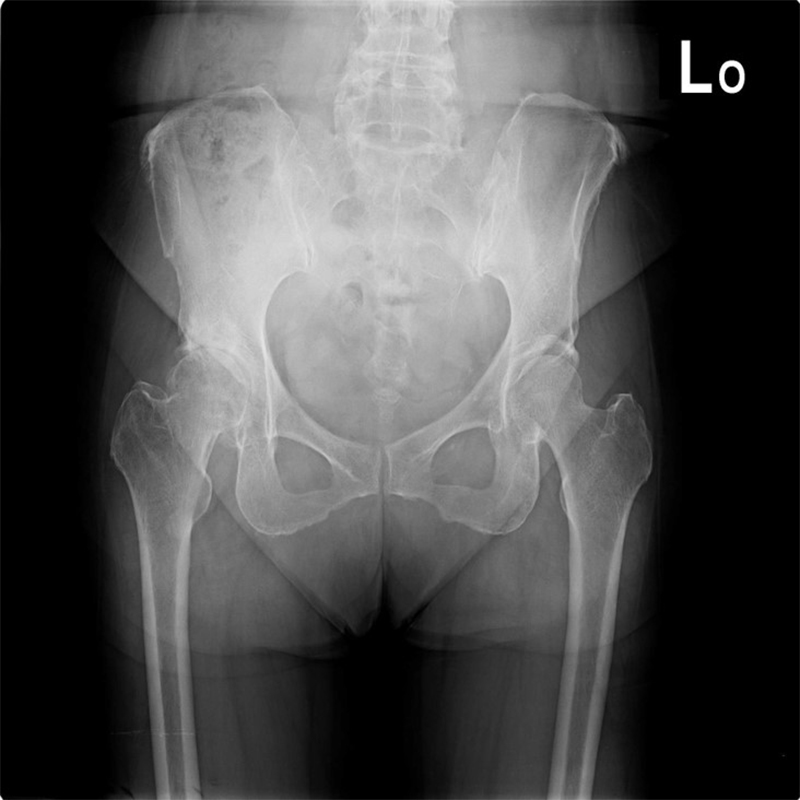

機器手臂手術 首頁 案例分享 髖關節手術 機器手臂手術 72歲 楊女士 退化性關節炎 術前 術後 60歲 彭先生骨股頭壞死 術前 術後 53歲 王女士退化性關節炎(DDH先天發育不全 CROWE TYPE 2) 術前 術後 83歲林女士退化性關節炎 術前 術後 83歲林女士退化性關節炎 術前 術後 楊女士 70歲 術前 術後 蔡女士 60歲 術前 術後